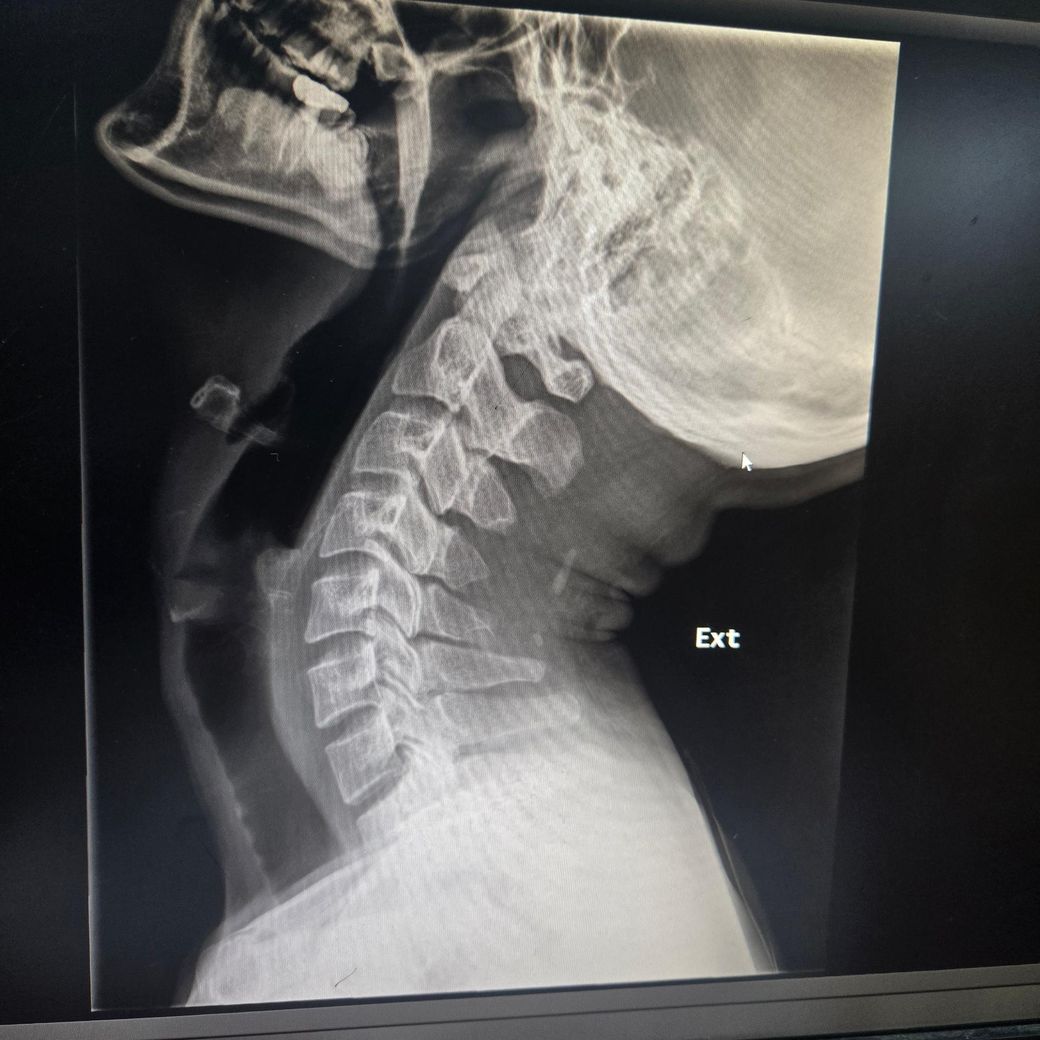

3달째 어지럼증과 경추1,2번쪽과 후두가 베개에 눌리거나 고개를 굽히면 눈도 울렁거리고 맥박도 느껴져요Xray사진인데 경추불안정증이 있나요? 부탁드립니다..경추mri 뇌mri mra 귀 눈 검사는 다 해봤지만 정상입니다.심리쪽 약도 먹었지만 변동없습니다.목 뻐근함과 같이 어지럼증이 왔습니다. 자고일어난후

경추불안정성의 경우 환자분의 경우 C1, C2 사이 거리 혹은 각도를 측정을 해야 합니다.

엑스레이 사진상 flexion과 extension에서 차이는 나지만 그것을 정량적으로 측정을 하기 위해서는

실제 엑스레이 사진으로 평가를 해야 합니다.